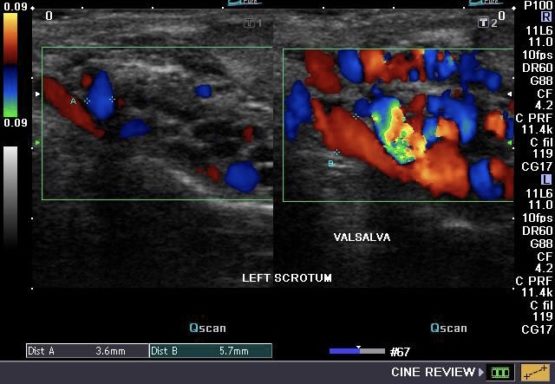

Κιρσοκήλη

Κιρσοκήλη ονομάζεται η ελικοειδής διάταση των φλεβών του όρχεως και πρόκειται για φλεβική ανεπάρκεια, όπως…